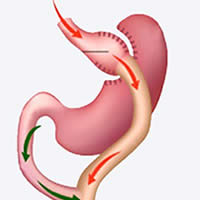

Bypass Gástrico Robótico

Jan.20.2020

¿En qué operaciones de Obesidad se recomienda realizar el Robot DaVinci?